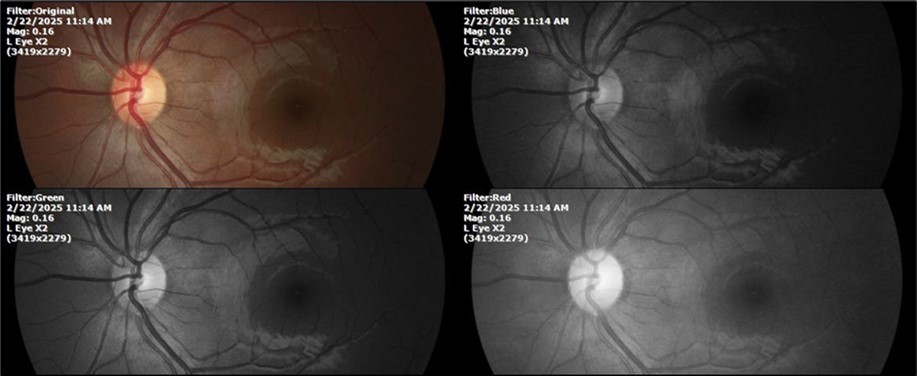

Figure 11.The photograph of the left eye does not show pathological data.

Figure 12. The photograph of the back of the eye, on the left side, shows a normal anatomy.

Figure 18.Mirror reflection of the eye on the left side, undisturbed.

Figure 19.The photograph of the fundus, on the left side, remains unaltered.

Figure 23.The mirror reflection of the left eye, without anomalies.

Figure 24.The eye that was not affected by the trauma (left side) remains in good condition.

Figure 28.The photograph of the left eye shows a specular reflection without pathology data.

Figure 29.The transparent media of the left eye does not show any alteration.

Figure 30.The anatomy of the posterior pole of the left eye is preserved, without showing pathology data.

Figure 34.The mirror reflection of the healthy eye (L. E.) continues within normal limits.

Figure 35.The anatomy of the anterior segment of the left eye is shown without alterations.

Figure 36.The retina, optic nerve, choroid, and macula of the left eye do not show any evidence of sympathetic ophthalmia.